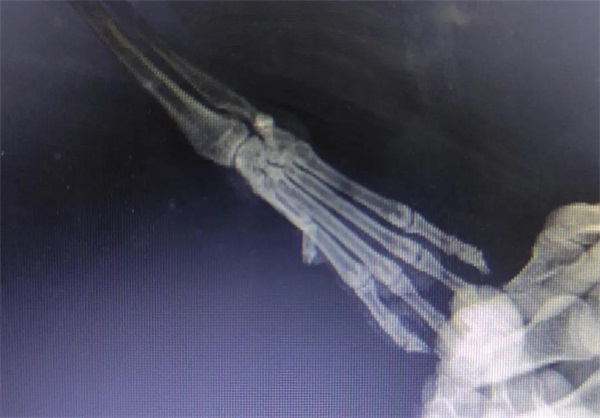

¡¡¡¡¾È»¤Ö°Ô±ÅжÏËüÊÇÐÛÐÔ£¬£¬£¬ £¬£¬£¬ÑdzÉÌå¡£¡£¡£¡£¡£ ¡£¡£» £»£»£»£»£» £»£»Øµ½¾È»¤ÖÐÐĺ󣬣¬£¬ £¬£¬£¬¾È»¤Ö°Ô±Á¬Ã¦¶ÔËüµÄÊÜÉ˲¿Î»¾ÙÐÐÁËX¹âÅÄÉã¼ì²é£¬£¬£¬ £¬£¬£¬É¨³ý¹ÇÕÛ¿ÉÄÜ£¬£¬£¬ £¬£¬£¬Ëæºó¶ÔÍâÉË´¦¾ÙÐÐÇå´´Ïû¶¾£¬£¬£¬ £¬£¬£¬·ìºÏÆÆËðÆ¤·ô¼°½Åµæ¡£¡£¡£¡£¡£ ¡£¡£Ö®ºó¾ÙÐÐÁËͨÀýÌå¼ì£¬£¬£¬ £¬£¬£¬È·Èϲ¢ÎÞÆäËûÎÊÌ⣬£¬£¬ £¬£¬£¬ÏȺóÔھȻ¤ÖÐÐĵÄÖÎÁÆÇø¡¢¿µ¸´ÇøÉúÑÄ¡£¡£¡£¡£¡£ ¡£¡£

·Å¹éǰÌå¼ì£º×óÊÖ»Ö¸´µÄºÜºÃ